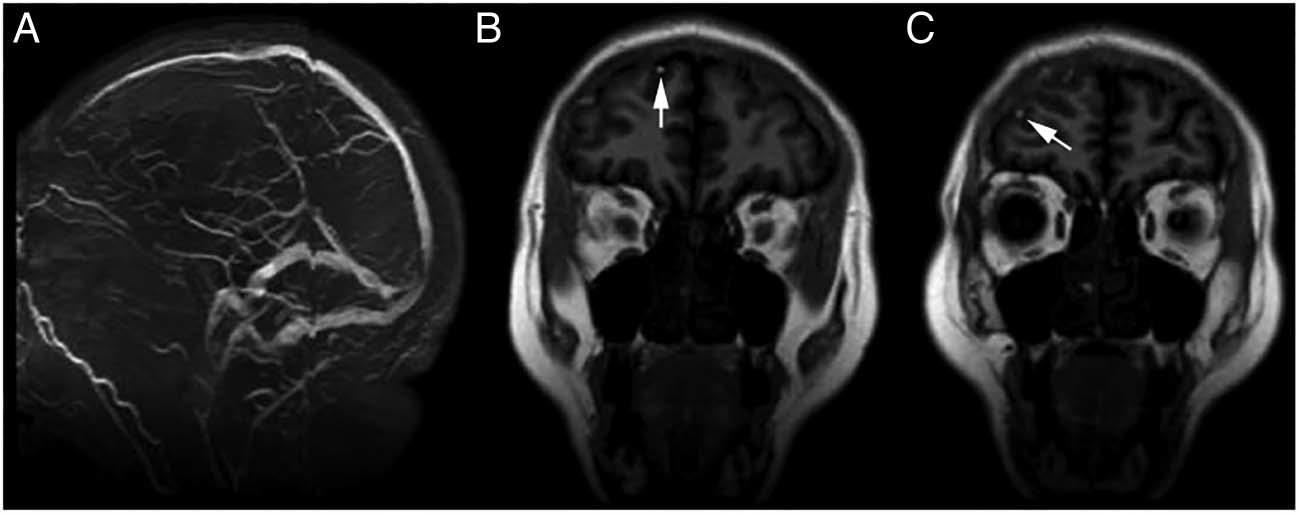

头颅平扫CT显示双侧额叶少量蛛网膜下腔出血(图1 A),但头颅CT未显示存在颅内动脉瘤。行头颅MRI检查,Flair像证实了蛛网膜下腔出血(图1 B),MRA检查显示正常(图1 C)。MRV排除了大静脉窦血栓形成的可能性(图2 A),而T1加权像证实了额叶皮层静脉血栓形成(图2 B,C)。给予患者肝素治疗后,患者头痛症状逐渐好转。

图2. MRV(A)证实颅内静脉窦正常,无血栓证据。冠状位Flair像显示右侧皮层静脉内高信号(箭头所示,B)以及皮层静脉血栓形成(C)